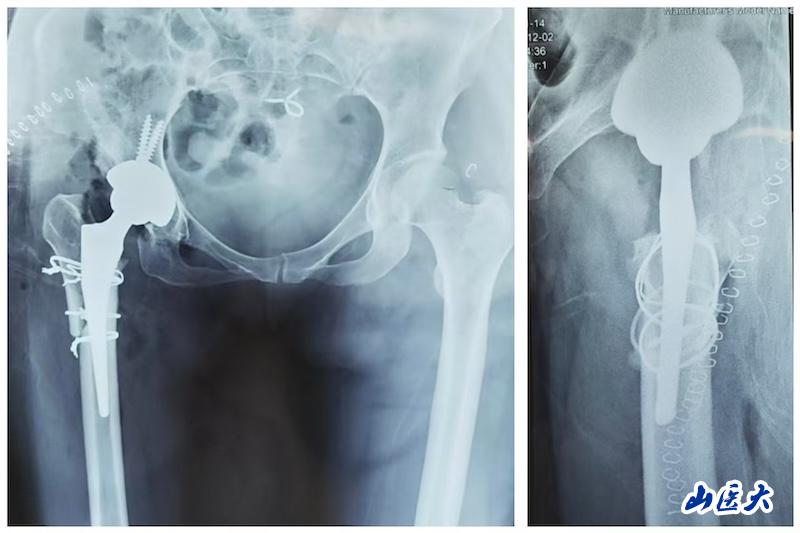

术后影像显示,该患者髋臼重建于真性髋臼,旋转中心得到恢复;股骨侧通过截骨重建,使用普通全涂层假体,同步矫正畸形、恢复偏心距,实现双下肢等长。

一位中年女性患者长期因髋部疼痛、步态严重异常、双腿长度不一而备受困扰。术前影像显示,其股骨头完全脱位,股骨发育异常,髓腔狭窄,前倾角显著增大,属于关节置换中难度极高的类型。发育性髋关节发育不良(DDH)的Crowe IV型高脱位,一直是对关节外科医生技术的严峻考验。此类手术需同步解决肢体延长、股骨畸形矫正、髋臼-股骨假体重建与软组织平衡等多重难题。

李春江主任团队采用的股骨近端截骨重建技术(亦称“尚氏截骨”),通过在粗隆间行长斜形截骨,重塑股骨近端形态,在矫正复杂畸形、调整肢体长度的同时,实现了“远端压配、近端适配”的稳定固定。该术式最大限度保护髋外展肌,截骨面接触广泛,骨愈合率高,为复杂髋关节畸形的重建提供了可靠选择。